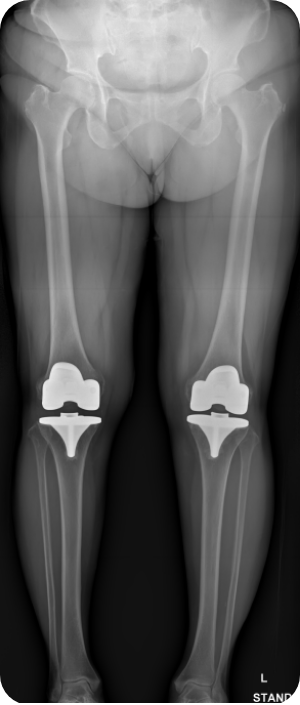

무릎인공관절 전치환술 사례2

• ▲ 수술 전

• ▲ 수술 후